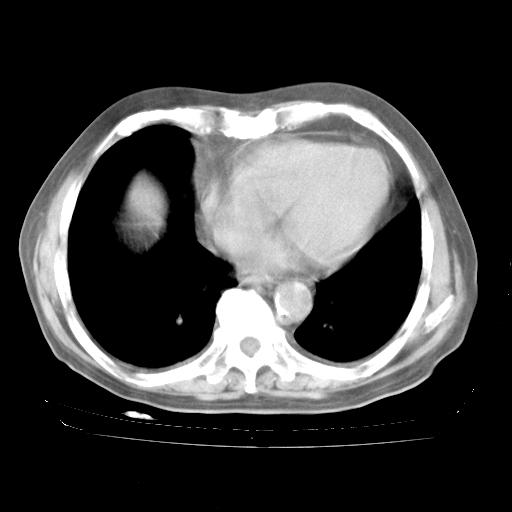

4月28日肺部CT——再次出现类似去年5月9日——透光度降低,“间质性”改变。

4月28日肺部CT——再次出现类似去年5月9日——磨玻璃样、间有“粟粒样”改变。

4月28日肺部CT

个人阅读4.14日肺部CT平扫:纵隔窗无异常,但肺窗示:双下肺内、后基底段有片絮状侵润影,部位以后基底段为著,以间质改变为主,呈急性肺泡炎征像,和首次住院影像学有相似之处。仅是个人读片,明日请相关专家再读片哈。其它建议同上。

1、108#的是4月14日的胸部CT(发此贴时还没看着28日的CT)。14日的胸部CT其实已经出现改变(如108#所述),个人认为28日的胸部CT除纵膈窗疑似有双侧胸膜增厚或少量胸积液(可行胸部B超明确)外,与4月14日对照病变有所加重;2、已经给予“异烟肼、利福平、乙胺丁醇”抗痨治疗?如果是,甲强龙80mg可缓慢减量;如果环磷酰胺已停用,暂不使用;3、中性粒细胞92%,明显升高,目前体温情况?注意合并细菌感染可能,使用左氧氟沙星情况下,是否联用B-内酰胺类抗菌药物?另外是查免疫全套非风湿全套。

今请临免主任会诊后认为:4月14日胸部CT已有双下肺间质性改变。患者病情复发多系激素减量过快不正规所致。目前甲强龙80mg/日,一周后酌情开始减量,不易过快。环磷酰胺若已停用,暂不使用。他同意目前抗菌药物使用,但应考虑是否加用B-内酰胺类抗菌药物(中性细胞明显增高);2、结核复发目前依据不足;3、若免疫全套各项指标正常,考虑多系特发性肺间质炎可能大。4、加强支持,并注意保护胃黏膜。

今上午去请教了临免、呼吸主任:1、介绍病史和阅读系列胸部CT一致认为:患者肺结核不考虑,仍为肺间质纤维化,目前处于急性肺泡炎阶段。2、若仍发热,可将甲强龙增至:80mg Bid静滴,同时鉴于中性增高,合并细菌感染可能,继续左氧氟沙星治疗,再联用B-内酰胺抗菌药物,如头孢哌酮--舒巴坦;3、停用抗痨药;4、目前甲强龙每日剂量160mg ,体温正常后再酌情减量;目前暂不用免疫抑制剂;4、不建议使用免疫增强剂等;5、加强支持治疗,鼓励患者进食;5、注意随访肝、肾功及血常规情况;6、因患者目前激素用量较大,加用胃黏膜保护剂,防止消化道出血可能。